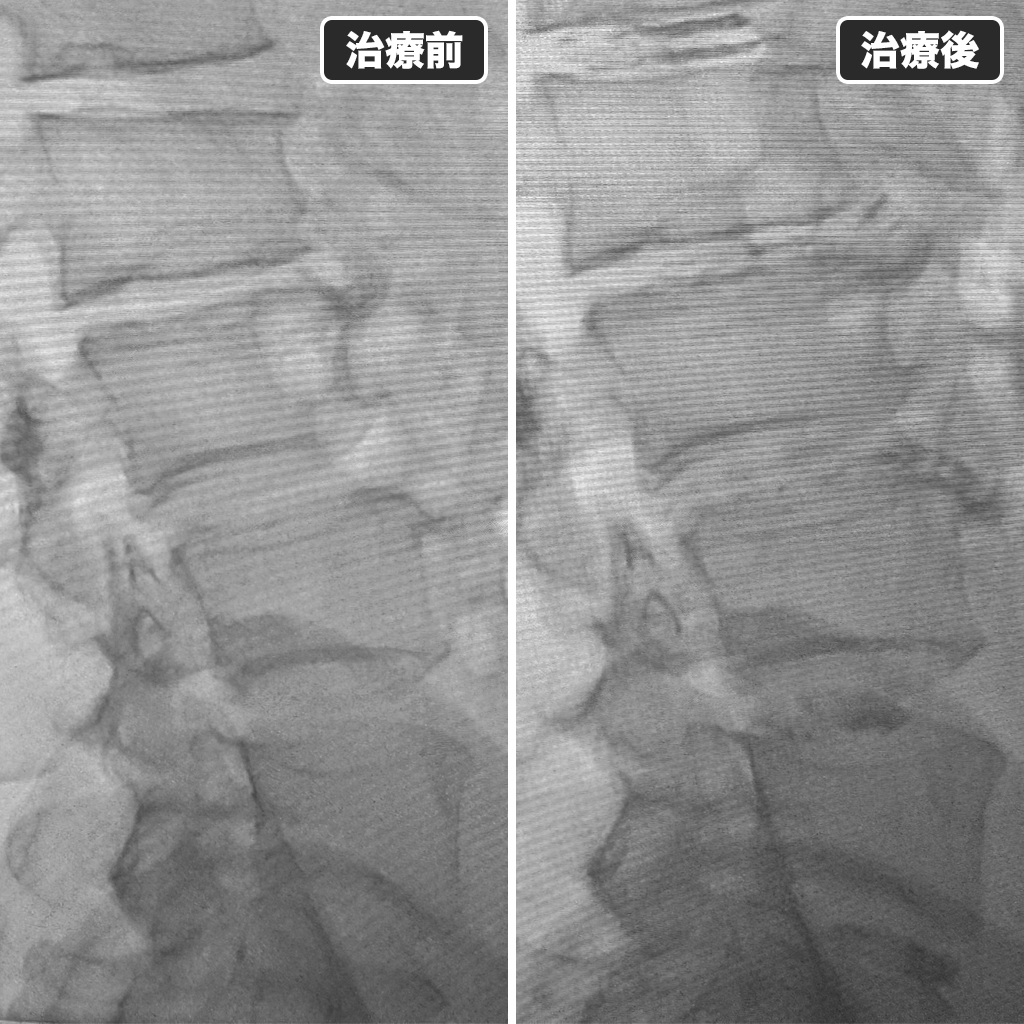

治療前後のレントゲン

治療前後のレントゲン写真です。左側側が治療前、右側が治療後になります。お仕事がIT関係であり、デスクワークが多い様でしたので30分おきにストレッチをされるように指導させて頂きました。